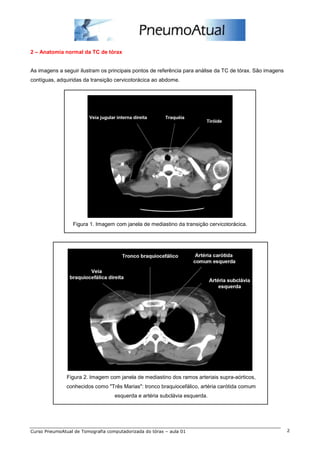

2 – Anatomia normal da TC de tórax

As imagens a seguir ilustram os principais pontos de referência para análise da TC de tórax. São imagens

contíguas, adquiridas da transição cervicotorácica ao abdome.

Figura 1. Imagem com janela de mediastino da transição cervicotorácica.

Figura 2. Imagem com janela de mediastino dos ramos arteriais supra-aórticos,

conhecidos como "Três Marias": tronco braquiocefálico, artéria carótida comum

esquerda e artéria subclávia esquerda.